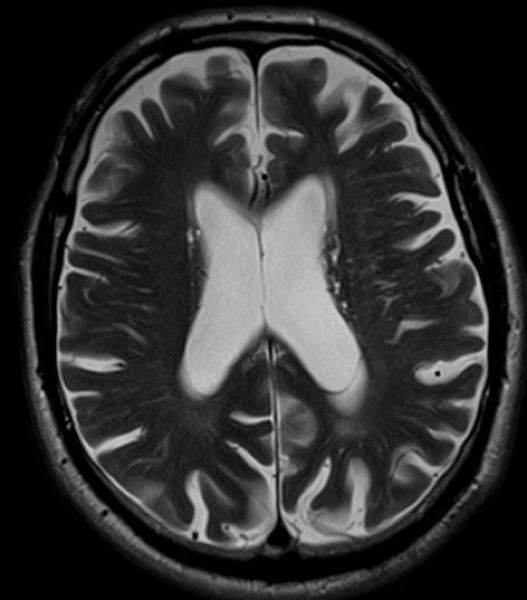

Хроническая ишемия головного мозга и лейкоареоз: симптомы и лечение